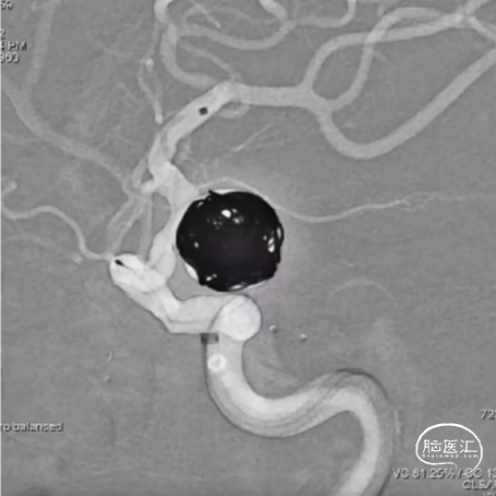

经测量可得动脉瘤宽度平均值为7.28mm,动脉瘤最小高度为4.91mm,参考尺寸选择表,选择WEB™ SL 8*4。

绝对瘤颈宽,右侧P1与瘤颈部分融合,容易疝出从而遮挡P1,应提前进行“分支保护”。

经VIA™微导管推送并释放WEB™ SL 8*4。

6个月后随访,Boss评分0级,动脉瘤完全闭塞不显影,WEB™完全栓塞。